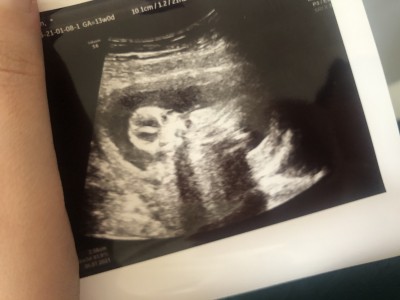

Cinsiyet tahmini lütfen

Arkadaşlar doktorum goremedı 1 ay daha nasıl sabredicem anlayan var mı?

Gebelik haftası

13

Erkege benziyo cnm

Banada kıza yakın dedı ama bellı edemem dedı

Kiz bence

Burdan kımse anlayamaz cnm bnde 13 te gttm cok kucuk tahmın edemem dedı 16 haftanda gel dedı insan merak edıyor ama beklemek lazım

Buyuk ihtimal kızdır canim erkek illa biyerden gösteriyor pipisini